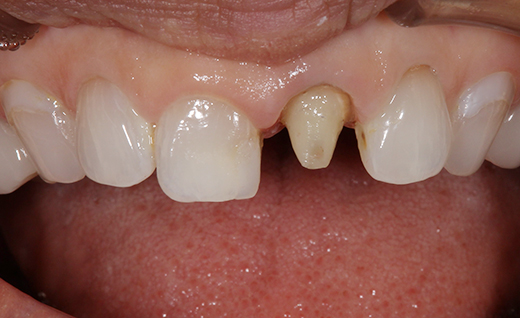

施術中

施術中コメント

施術中の様子です。 保険の被せ物を外し、新しいオールセラミッククラウンを装着するための土台を丁寧に形成していきます。 「少し緊張していましたが、説明がわかりやすくて安心できました」とのお言葉もいただきました。